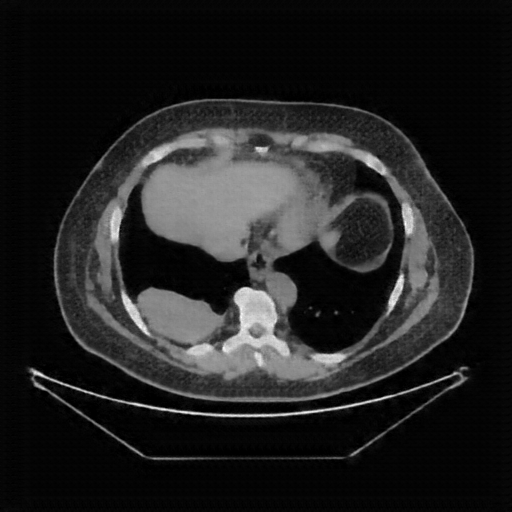

Original VENOUS CT scan

Full window (WL 1023.5, WW 4095 β†’ Low βˆ’1024, High +3071)

Actual HU range: [-160.0, 240.0]